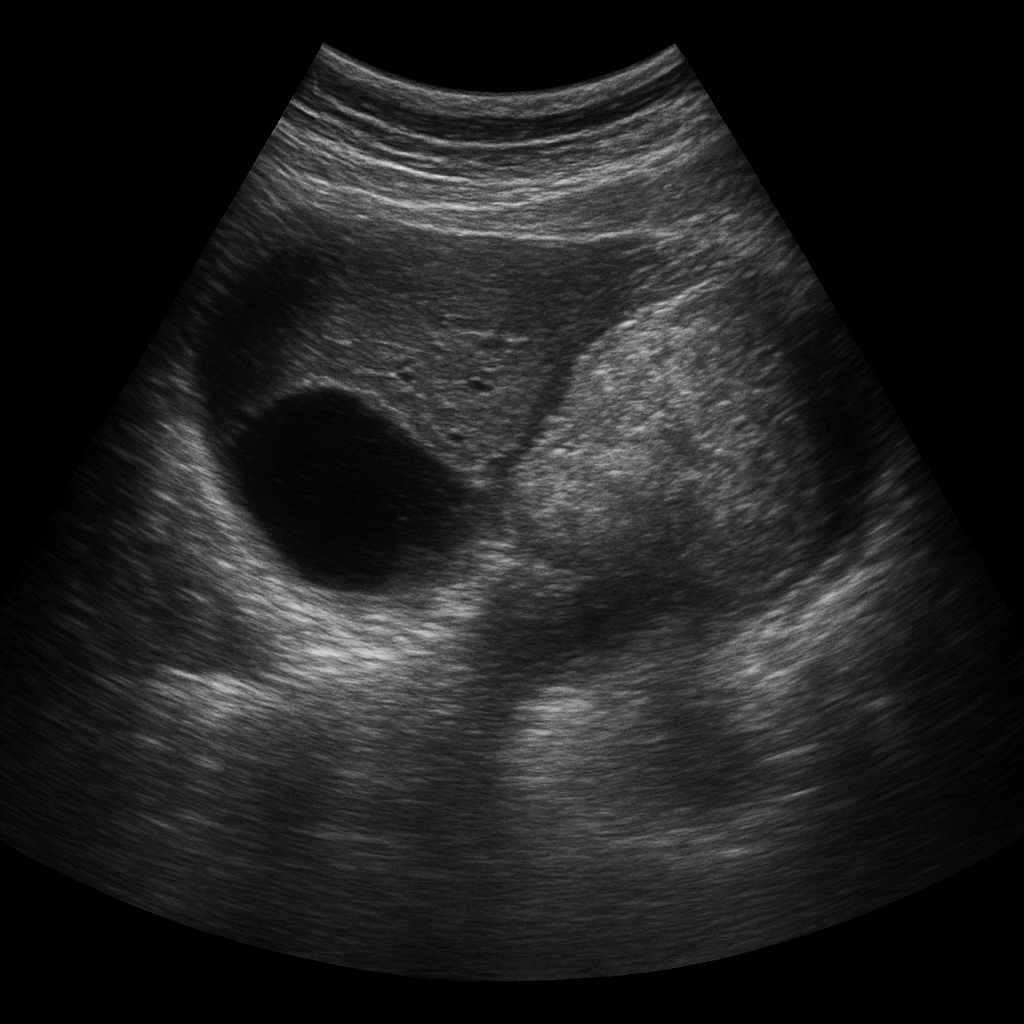

L’échographie abdominale repose sur l’émission d’ondes ultrasonores à haute fréquence à travers une sonde, appliquée sur la peau. Ces ondes se propagent à travers les tissus et sont réfléchies différemment selon la nature des structures qu’elles rencontrent (liquide, tissu dense, gaz, os). Le signal de retour est interprété par un logiciel informatique qui crée des images en temps réel.

Le radiologue, ou le médecin échographiste, peut ainsi observer l’aspect des organes, rechercher des anomalies morphologiques, mesurer des structures et, dans certains cas, guider des gestes diagnostiques ou thérapeutiques.

1. Le foie

L’échographie hépatique permet d’évaluer la taille, la structure (stéatose, nodules, tumeurs), la texture (cirrhose), et la vascularisation du foie. Elle est utile dans le suivi des hépatopathies chroniques.

2. La vésicule biliaire

On y recherche des calculs biliaires (lithiases), une inflammation de la paroi (cholécystite), ou des polypes. Cet organe est facilement accessible par échographie, notamment après un jeûne.

3. Les reins et voies urinaires hautes

Les reins peuvent être explorés à la recherche de calculs rénaux, de kystes, de tumeurs, ou encore d’une dilatation des cavités rénales (hydronéphrose). On peut aussi y dépister une malformation congénitale ou une infection (comme une pyélonéphrite), bien que le diagnostic repose avant tout sur la clinique et le scanner.